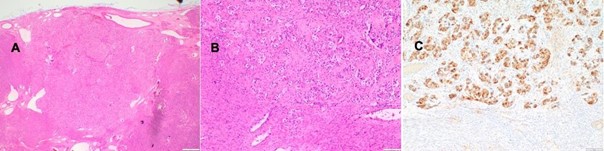

The histological examination revealed a 7.5 cm diameter mesenchymal tumor located in the left parametrial region, displaying extensive superficial capsular defects infiltrating the left pelvic wall. A subsequent pathological analysis identified a high-grade TFE3-associated PEComa. Immunohistochemical analysis of the specimen demonstrated subserosal tumor positivity for HMB-45, cytokeratin, AE 1/AE 3, and calretinin, with weak positivity for smooth muscle actin (SMA). Conversely, the tumor tested negative for Cytokeratin 5, D2-40, CD34, Melan A, and S100. The proliferation rate (Ki-67) within the tumor tissue was observed to be up to 5%, with weak, inconclusive positivity for PAX8.

The uterine PEComa exhibited a high-grade morphological presentation characterized by the absence of infiltrative growth patterns. Assessment revealed a mitotic rate of 3 per 50 high-power fields (HPF), devoid of necrotic areas and vascular infiltration. These observations collectively fulfill three malignancy criteria [2], thereby warranting classification as malignant according to both overarching and gynecologically tailored diagnostic standards.

Figure 2: Histopathologic finding in the 1st case A Diffuse proliferation of epitheloid cells with clear cytoplasm and hyaline stroma; HE staining, magnification x40. B The tumor cells show heterogenous (membranous) staining with anti-CD56; magnification x200. C A large fraction of the PEComa cells are positive for anti-estrogen receptor (nuclear staining); note the mild nuclear atypia; magnification x200.

Figure 4: Histopathologic findings in the 2nd case A Overview with numerous large PEComa cells displaying clear cytoplasm; HE staining, magnification x20. B Nests of PEComa cells within a fibroblast-rich and hyaline stroma; HE staining, magnification x100. C As in this case, PEComa cells typically show diffuse and strong positivity for anti-HMB45; magnification x100.